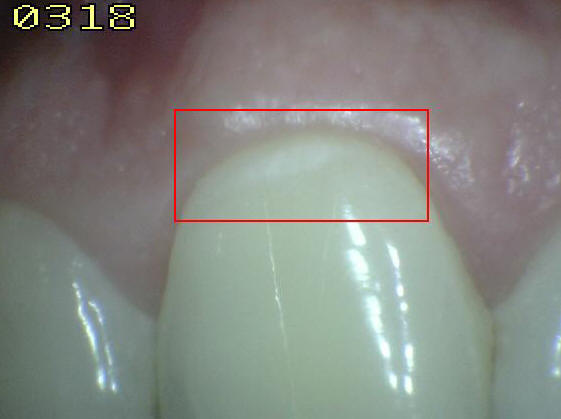

Código 3